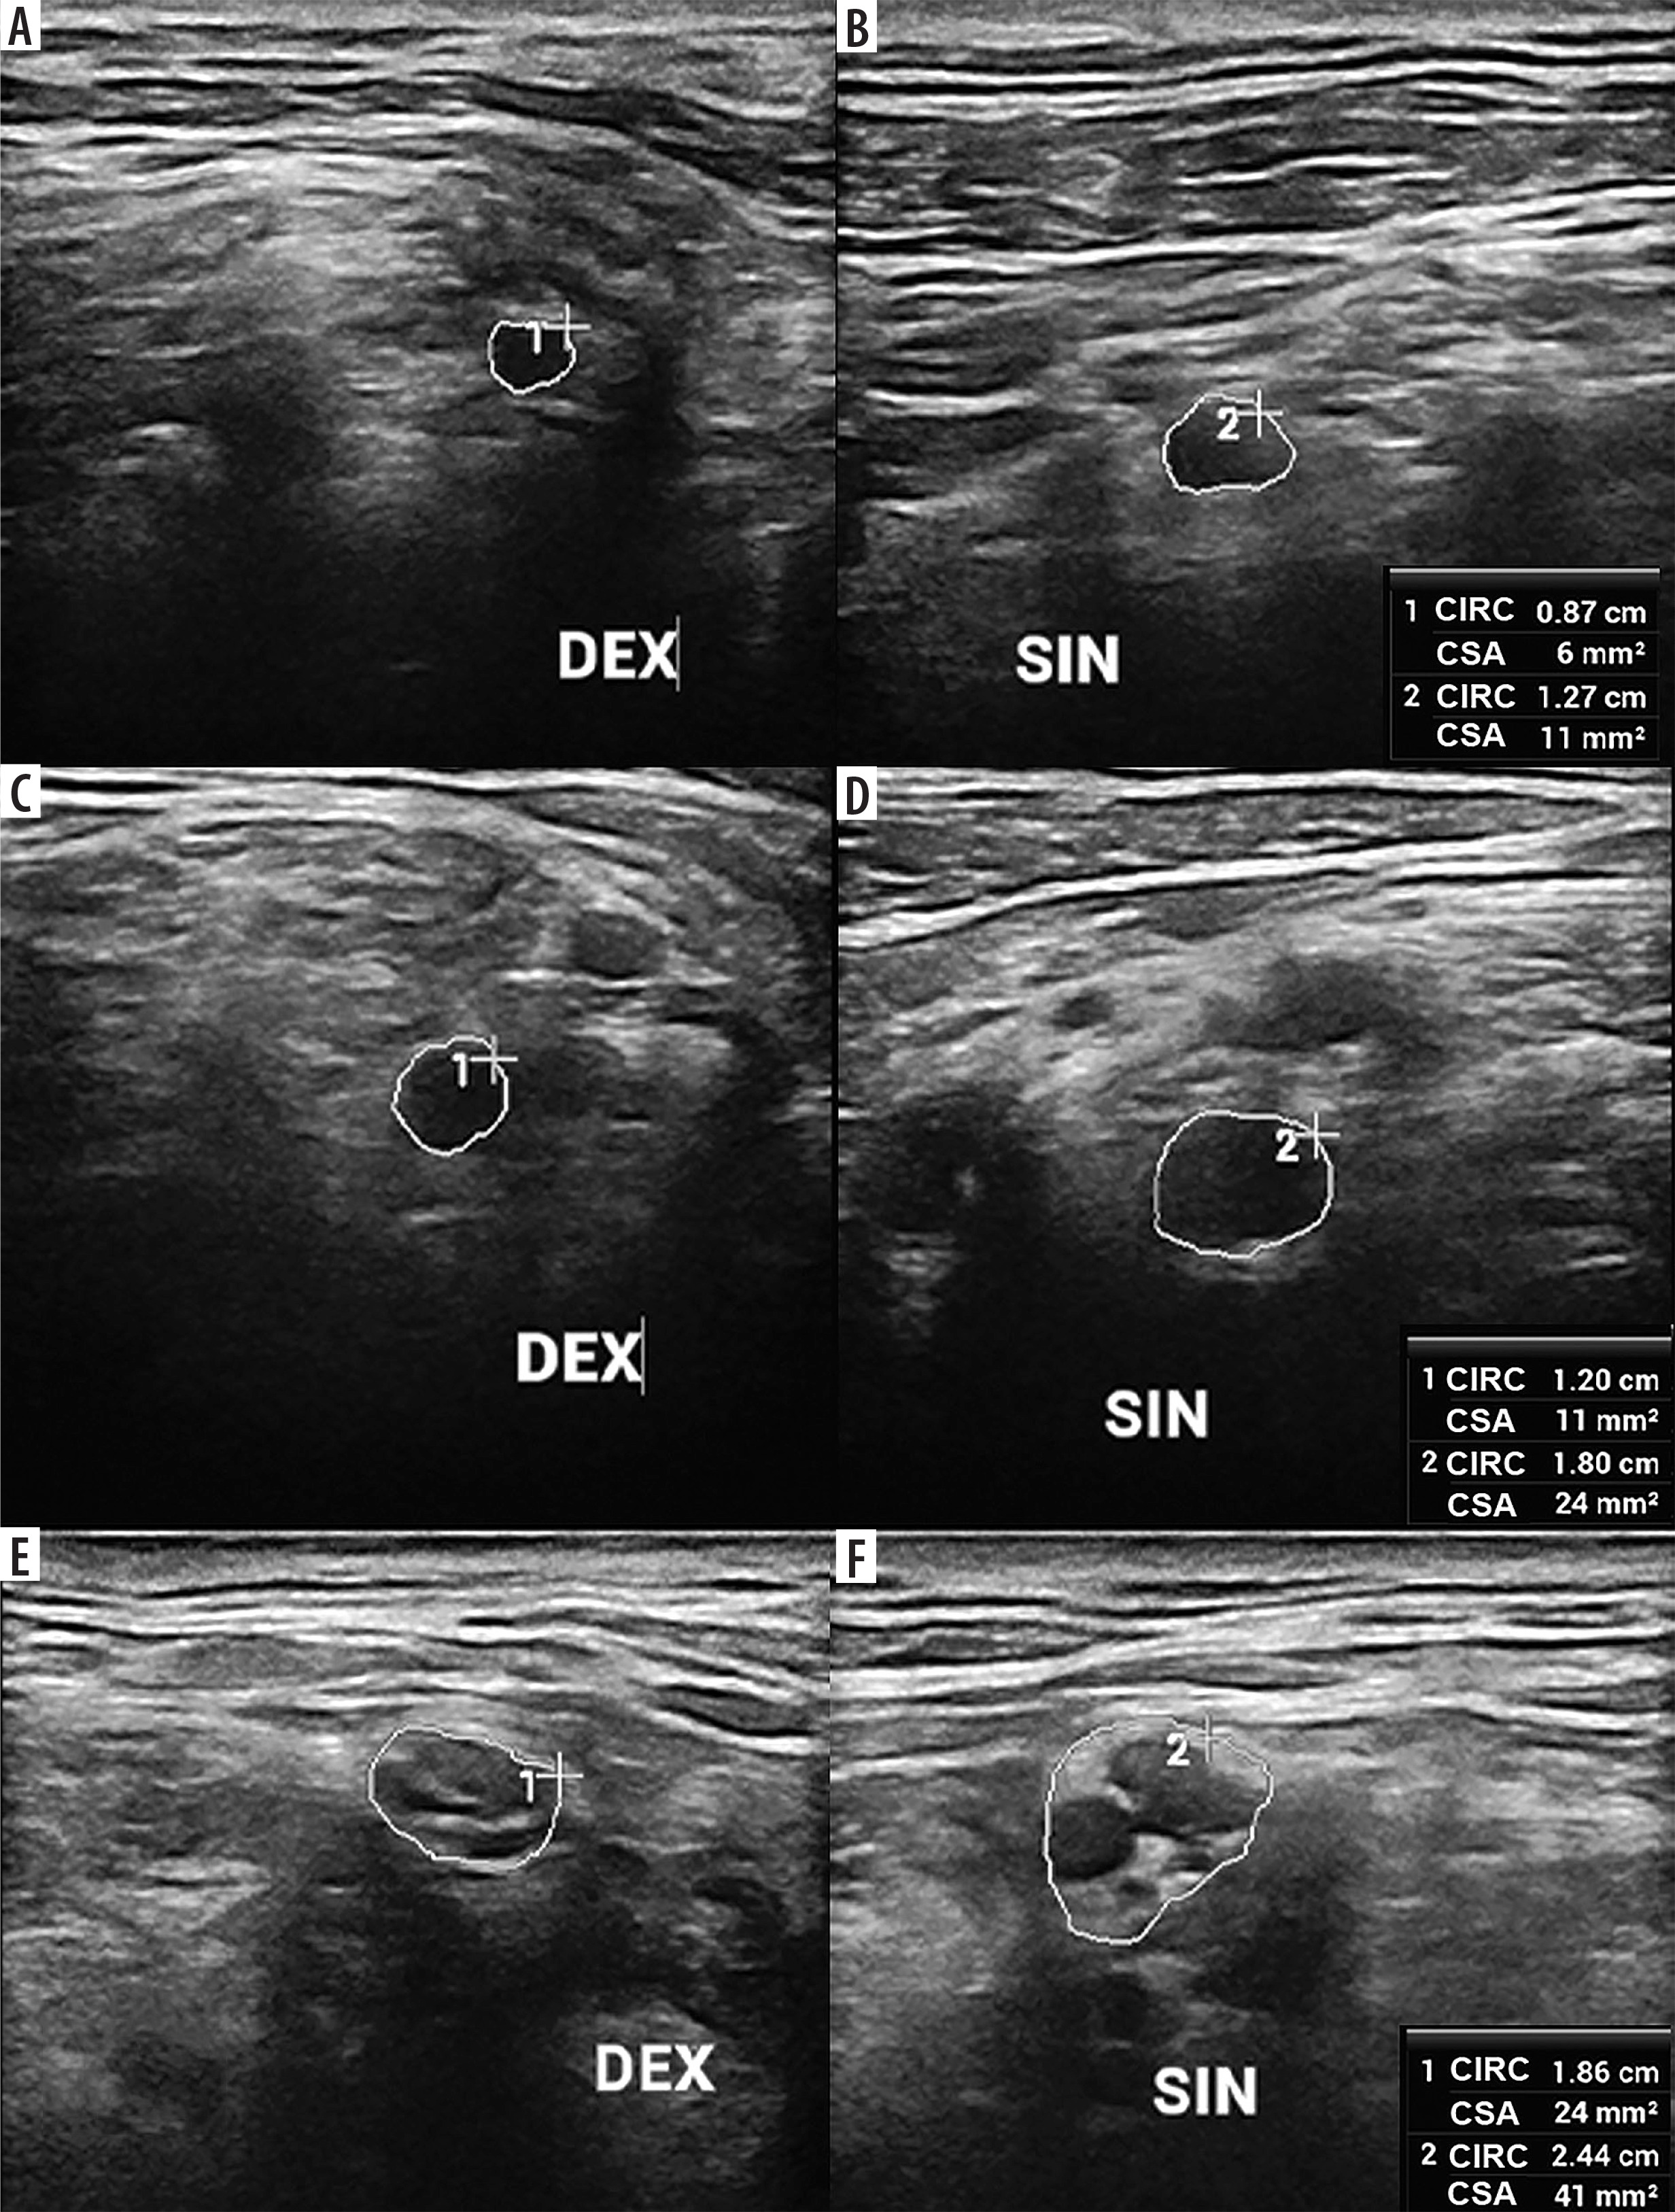

Figure 6

High-resolution ultrasound (HRUS) image of the C5 (A, B) and C6 (C, D) roots and upper trunk (UT) (E, F) in 66-year-old patient with the left upper limb paresis due to neuroborreliosis with Banwarth syndrome. Side-by-side comparison with increased measurements on the symptomatic side. Images obtained by author with a 5-20 MHz linear probe of the Mindray Resona I9